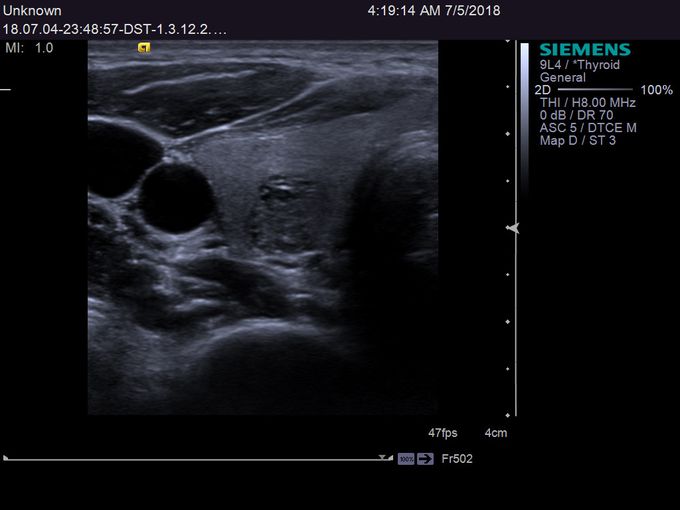

Кроме новой техники, можно заказать восстановленные медицинские системы: ультразвуковые сканеры, томографы, флюороскопы, ангиографы и хирургические установки С-дуга.